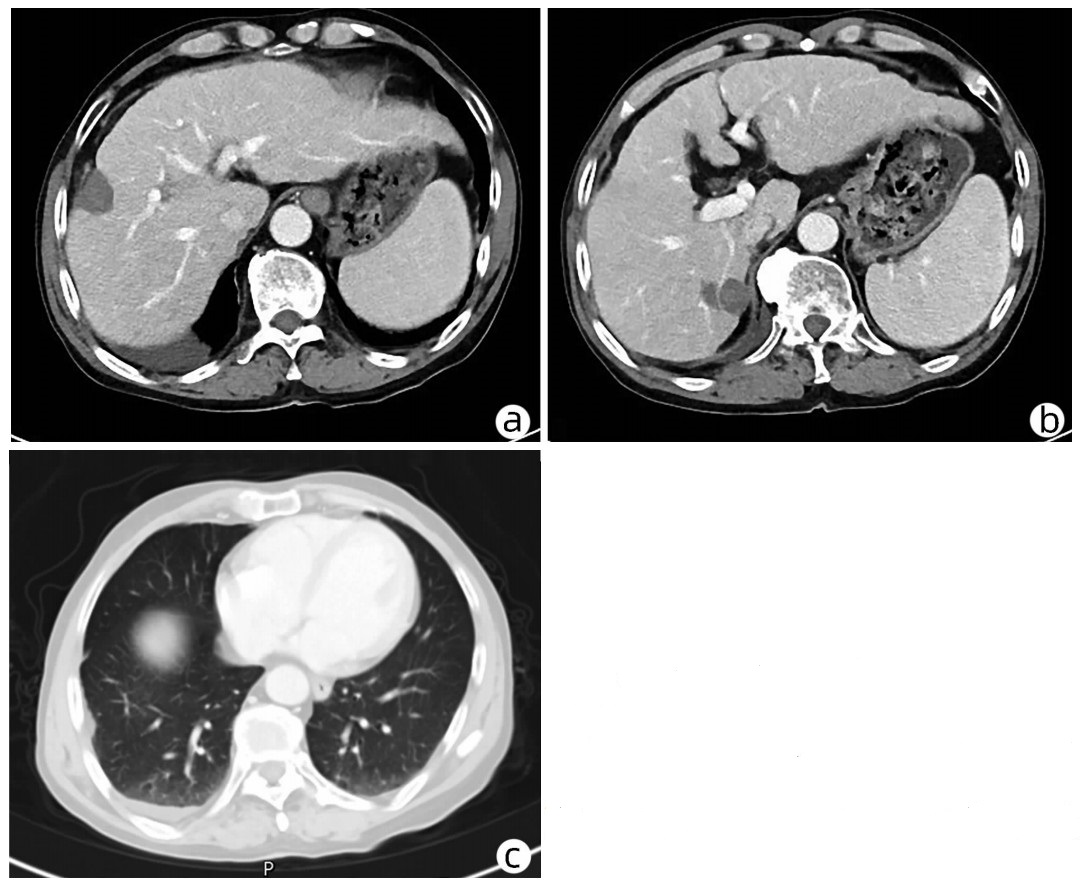

Late-onset diaphragmatic hernia after microwave ablation of hepatocellular carcinoma: A case report

Xiaodong WANG, Yurong ZHANG, Xiaoning ZHU, Ding ZHENG, Jing WANG

2022, 38(8): 1875-1877. DOI: 10.3969/j.issn.1001-5256.2022.08.029

Abstract(834) HTML (321) PDF (2572KB)(47)

Abstract: